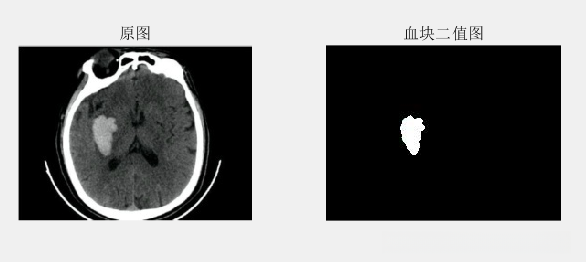

subplot(121);imshow('3.jpg');title('原图');

subplot(122);imshow(binary_image_cleaned);title('血块二值图');

代码解读

截止到目前,已经实现了对血块的分割与提取。接下来是计算。